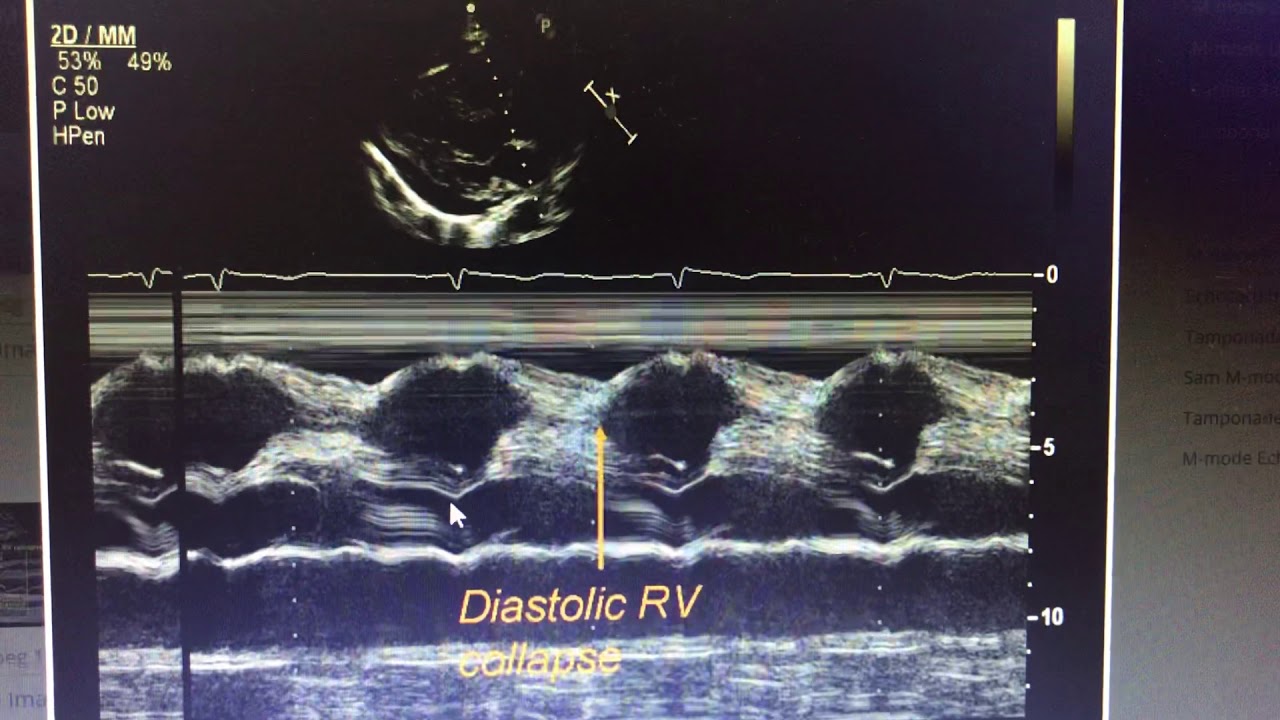

Cardiac Tamponade CCM Daily